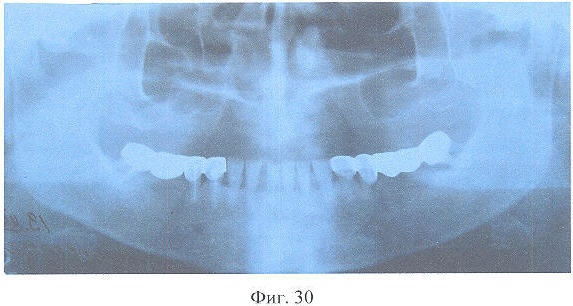

На фиг.30 – рентгенограмма больной Л. до лечения.

Больной в толщу тел верхних челюстей введено семь, нижней – три дентальных имплантатов из никелида титана с пористой шейкой (Пат. РФ №2098043, М.кл. А61С 8/00, 1995 г.). Через 3,5 мес. изготовлены несъемные металлокерамические зубные протезы с опорой на дентальные имплантаты согласно разработанному способу.